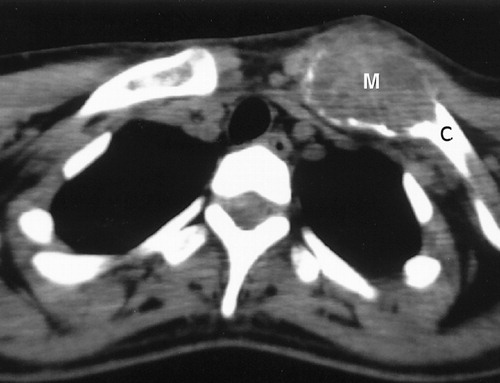

Tumors in the Chest Wall typically manifest as painful, quickly growing and easily palpable masses. Surgery is often necessary, and may be followed by plastic surgery reconstruction to recreate a normal appearance.

Treatment options will depend upon the type of Chest Wall Tumor found. If the tumor is benign, no treatment may be required, although at times, proving that a chest wall tumor is benign requires that it be removed (excisional biopsy).